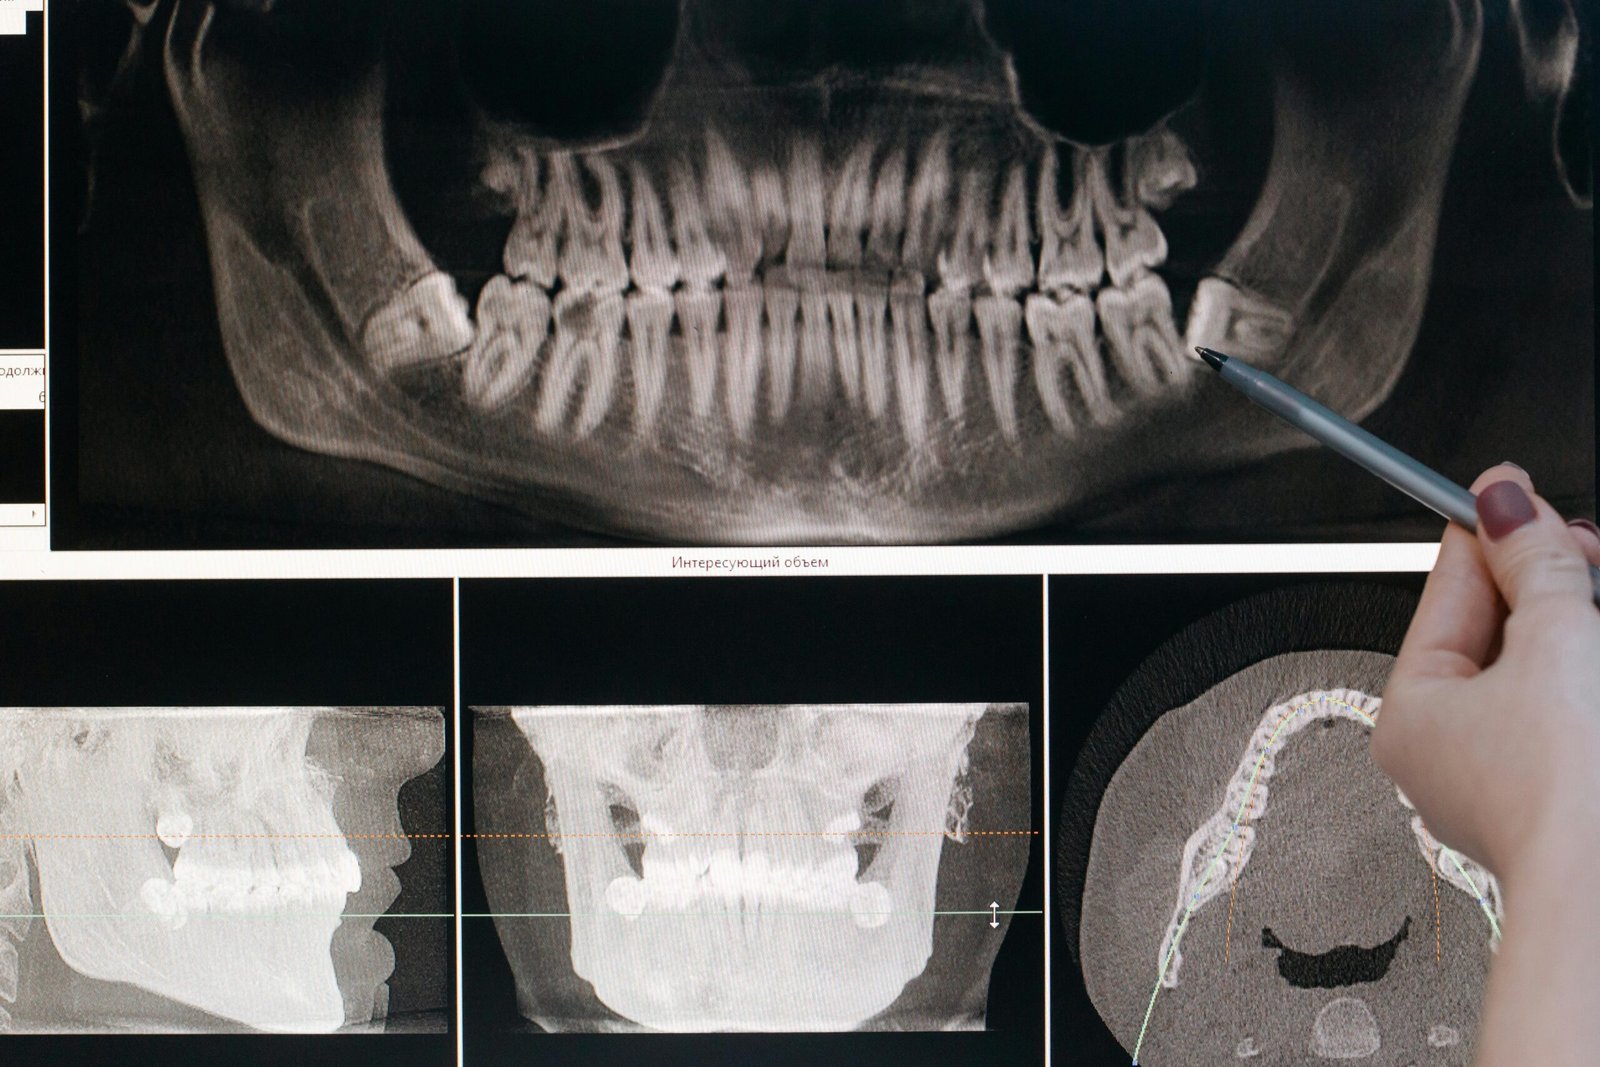

Quick, clear, and low-radiation digital X-rays

Digital Dental X-Ray | Safe & Accurate Imaging.

Experience safe, low-radiation digital X-rays at Khan Dental Care. Get fast, accurate results for better diagnosis and personalized dental treatment.